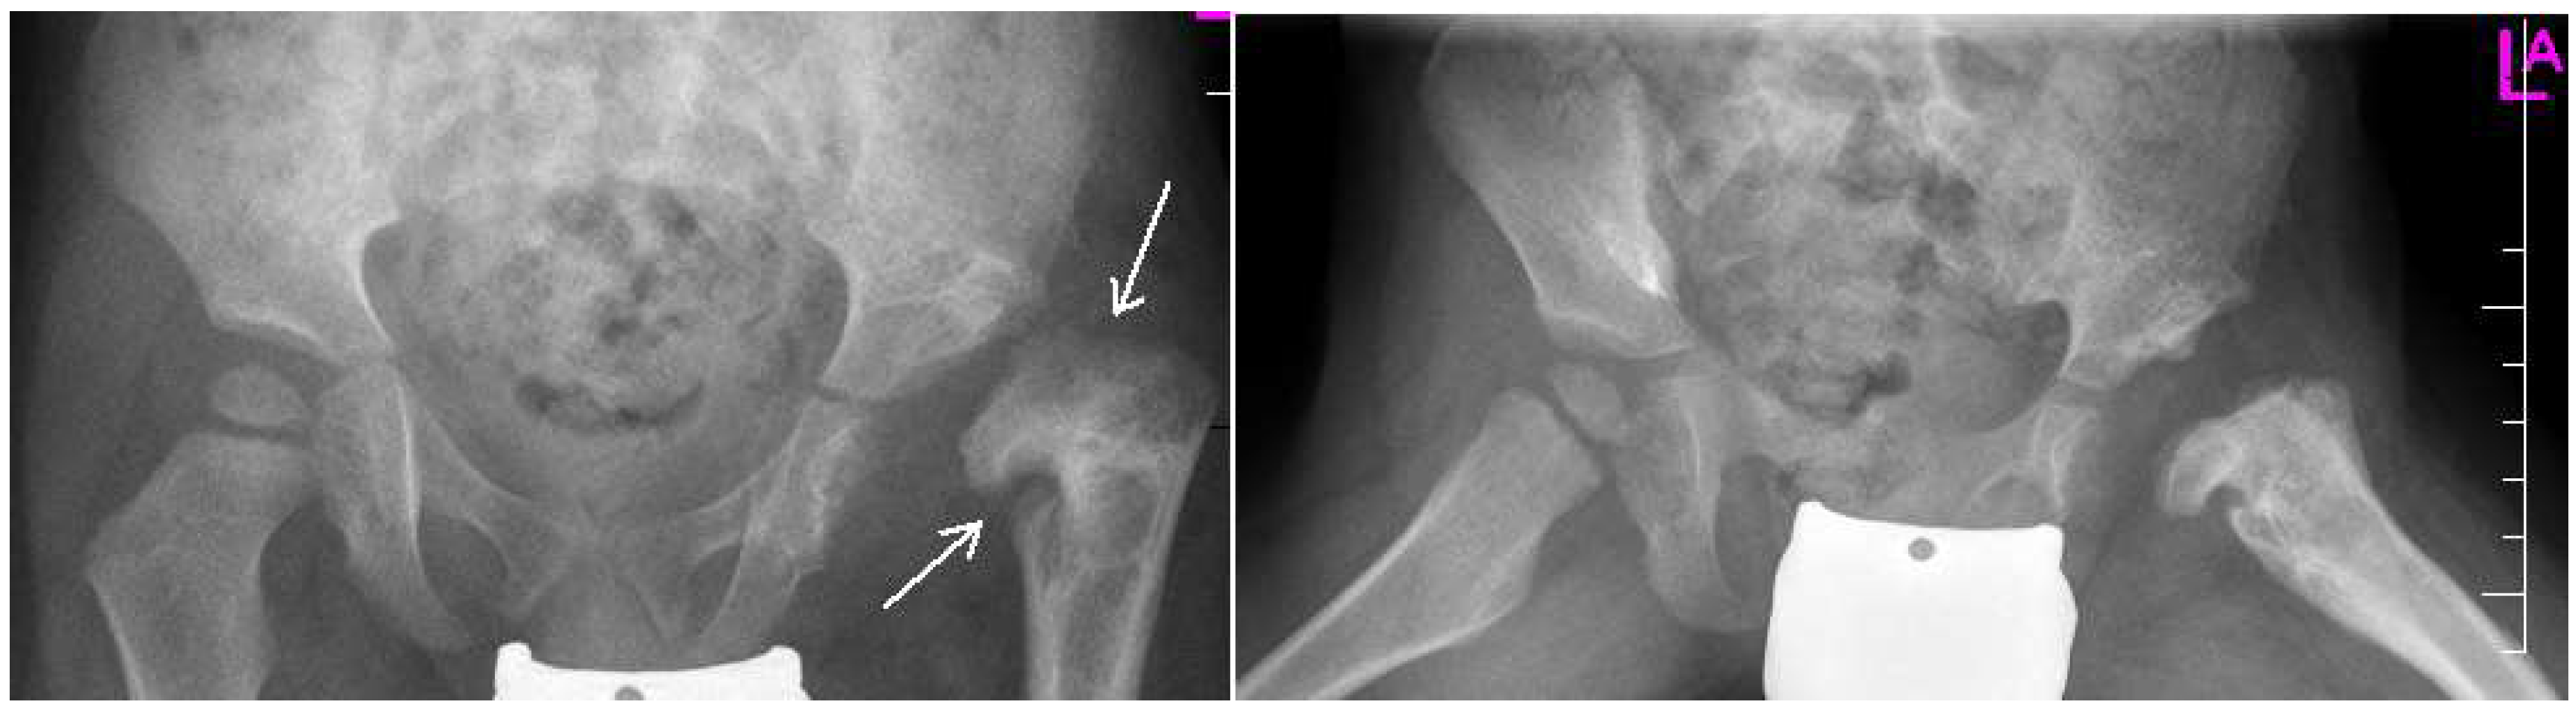

Figure 2.

Radiographs: Antero-posterior (AP) and Lauensteun view of three weeks old child’s left hip, slightly out of the socket (eccentric hip).

Figure 3.

Radiographs: AP and Lauensteun with postrezidual deformity in the same patient after 2 years.